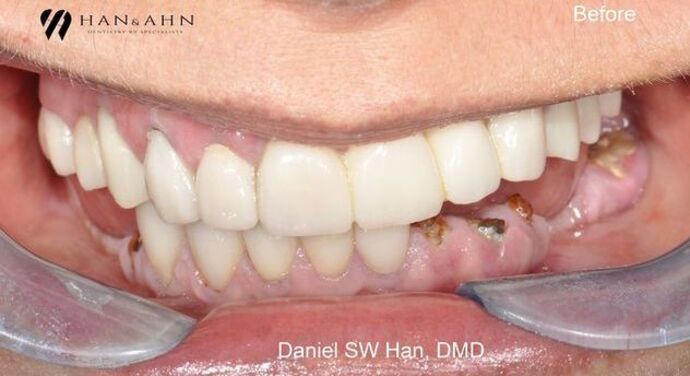

Full Mouth Reconstruction: Case 3: Teeth in One Day

Mandibular full mouth reconstruction was done in one day (Teeth in One day). The patient has had asymmetric bite and smile. This caused bite collapse and TMJ issues for many years. The patient was treated with several dental implants to reconstruct the mandibular teeth back in one day. This 'Teeth in One Day' procedure is possible for almost every patient; however, the case must be carefully selected and prepared prior to the actual treatment day.